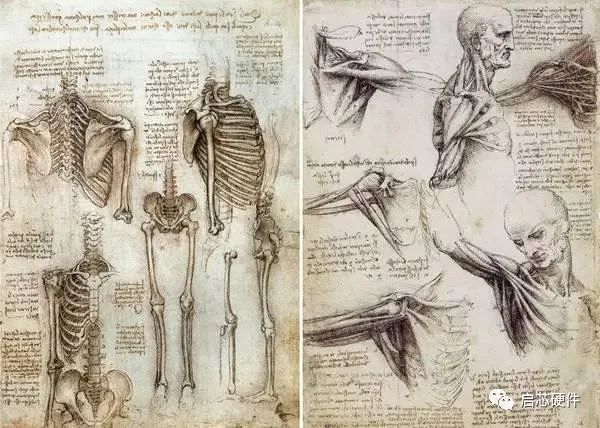

1. 人体解剖图– 达芬奇(1509-1510)

没有相机的时候,手绘就有可照片的效果。在达芬奇的年代,没有人会系统地制作人体内外结构的图片,但达芬奇却用超过200张绘图,运他的绘画技术,为现代解剖学作了一个重要的奠基石。